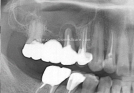

Clinical Cases

• Case1

• Case2

• Case3

• Case4

• Case5

• Case6

• Case7

• Case8

• Case9

• Case10